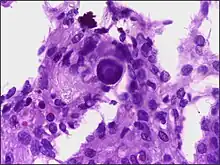

Psammoma body

A psammoma body is a round collection of calcium, seen microscopically. The term is derived from Greek άμμος (ámmos) 'sand'.

Psammoma bodies usually have a laminar appearance, are circular, acellular and basophilic.